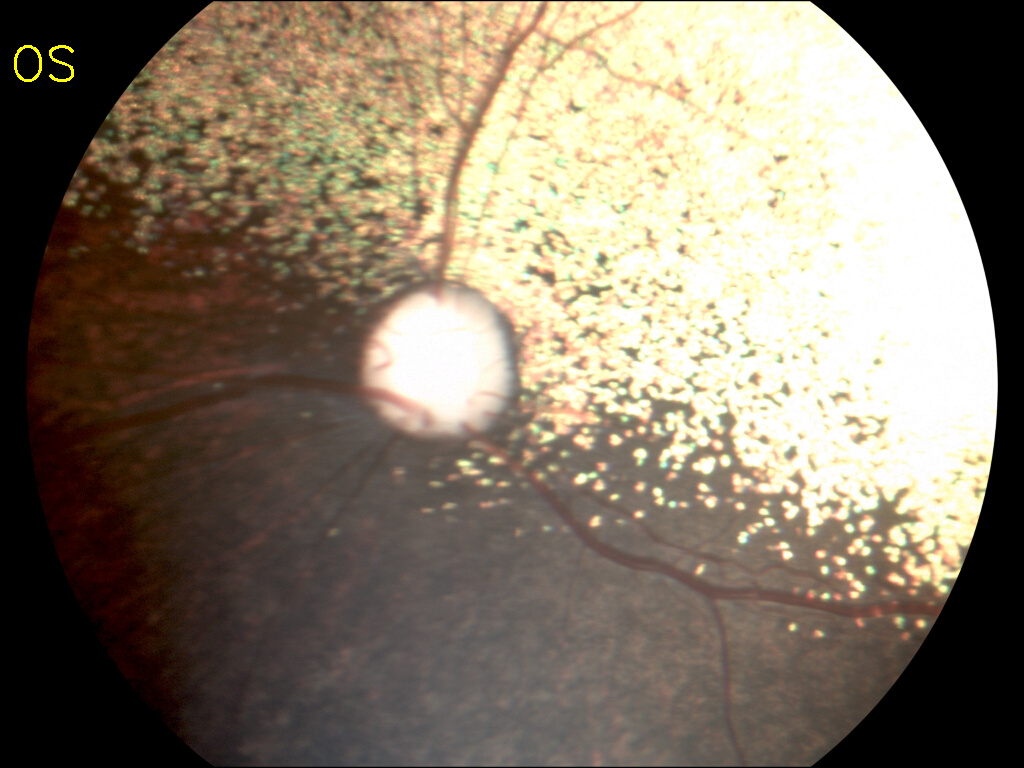

При воздействии на фоторецепторы сетчатки светом разной длины волны оценивается состояние зрачка. У здорового животного происходит сужение зрачка на синий и красный свет. При заболеваниях сетчатки или поражениях головного мозга данные изменения зрачка могут не происходить. Ветеринарный врач-офтальмолог делает определенные заключения.